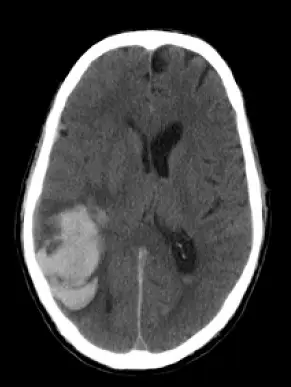

一位70歲男性,於晚飯後劇烈頭痛頭暈及噁心嘔吐,被家人送來急診,電腦斷層檢查結果如圖,下列敘述何者錯誤?

非造影軸向腦部 CT 可見右頂葉皮質下區塊狀高密度病灶,密度約 80–100 HU,周邊伴隨低密度暈周水腫,並造成輕度中央結構移位。病灶位於大腦皮質與皮質下白質交界處,形狀較圓鈍、邊緣較為清楚,且位於葉狀(lobar)區域,非深部基底節或橋腦。此分布提示非典型高血壓性深部出血,應考慮其他次發性出血原因。